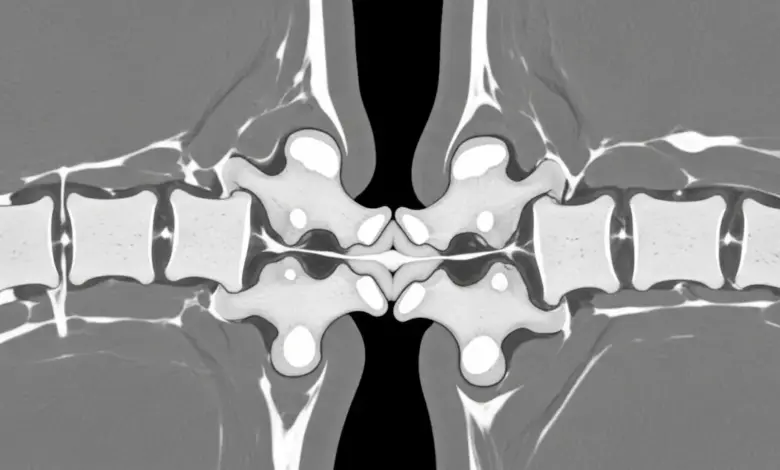

Diagnóstico por imagem e exame físico

No exame, a palpação entre os processos espinhosos pode reproduzir a dor.

Radiografias revelam aproximação e esclerose das superfícies, ressonância magnética mostra edema da bursa interespinhosa e sinais inflamatórios, enquanto a tomografia detalha o contorno ósseo e pseudoarticulações.

Muitos pacientes têm achados degenerativos associados, por isso, a correlação clínica é indispensável na doença de Baastrup.